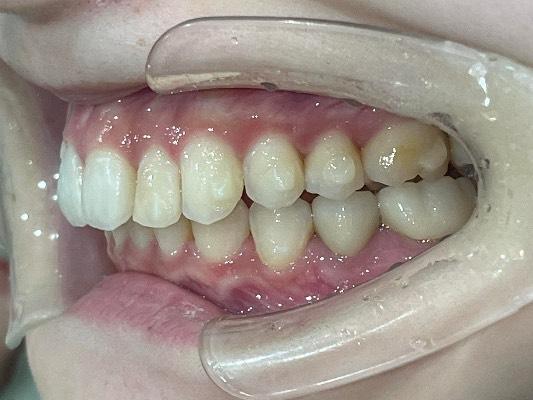

CASE 10

BEFORE

▶

AFTER

20代。 「前歯がデコボコしているのが気になる」「笑った時に歯並びが悪く見える」というお悩みでご来院。 仕事やプライベートで目立つワイヤー矯正は避けたいとのことで、透明なマウスピース矯正をご希望されました。